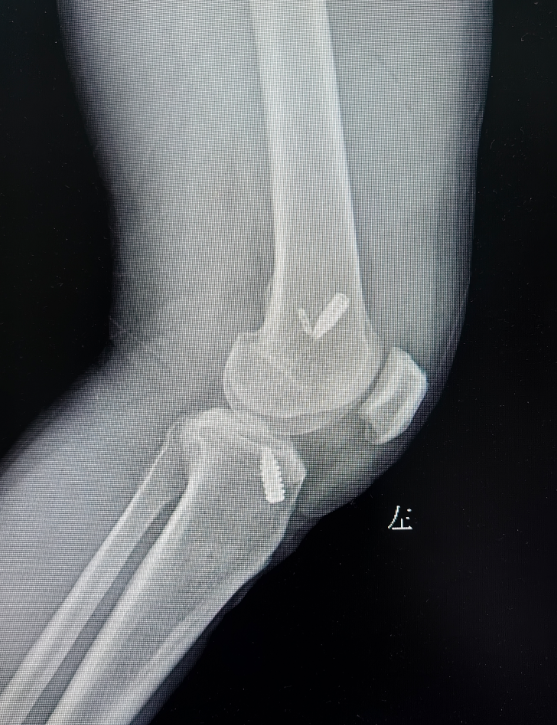

▲术后DR复查影像